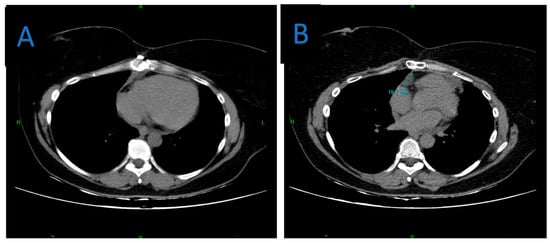

A Rare Case of Multilocular Mesothelial Inclusion Cysts of the Pericardium: Diagnosis, Treatment, Follow Up, with Comprehensive Review of the Literature

by Ali Shadmanian, Kosha Patel, Endre Alács, Henriette Gavallér, Szilva Agocs and Miklós Bitay

Background: Multilocular mesothelial inclusion cysts—also known as benign multicystic mesothelioma (BMM)—are rare, typically arising in the peritoneal cavity. Pericardial involvement is extremely uncommon and can pose diagnostic and therapeutic challenges due to their recurrent and infiltrative nature. Accurate diagnosis and surgical strategy are [...] Read more.

Background: Multilocular mesothelial inclusion cysts—also known as benign multicystic mesothelioma (BMM)—are rare, typically arising in the peritoneal cavity. Pericardial involvement is extremely uncommon and can pose diagnostic and therapeutic challenges due to their recurrent and infiltrative nature. Accurate diagnosis and surgical strategy are critical for management and recurrence prevention. Methods: We present the case of a 36-year-old woman with a prior history of malignant melanoma who developed recurrent multilocular cystic masses of the pericardium. Initial imaging with echocardiography, cardiac magnetic resonance (CMR), and computed tomography (CT) revealed multilocular pericardial cysts. Surgical resection was performed under cardiopulmonary bypass (CPB), but complete excision was limited due to epicardial infiltration. Histopathology confirmed a benign mesothelial origin. One year later, recurrence prompted a second surgical intervention with total pericardiectomy and Gore-Tex patch reconstruction. Results: Postoperative recovery was uneventful in both instances. Follow-up imaging at 6 and 12 months demonstrated no significant recurrence. Histological analysis confirmed benign cysts lined with mesothelial cells, positive for calretinin and WT-1. This represents one of the first documented living cases of pericardial BMM managed with staged surgery and total pericardiectomy. Conclusions: Pericardial BMM is a rare, benign, but potentially recurrent lesion. In cases of extensive or recurrent disease, total pericardiectomy may offer definitive treatment. Multimodal imaging, histopathological evaluation, and personalized surgical planning are essential for effective management. Full article

Show Figures

Figure 1